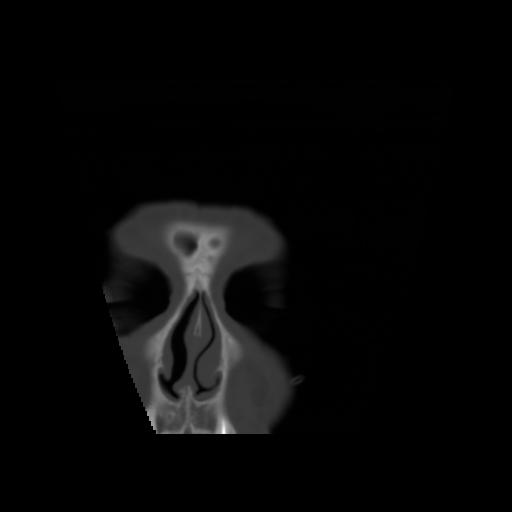

5 CEREBRO,,Coronal,3.000,CEREBRO,Coronal,